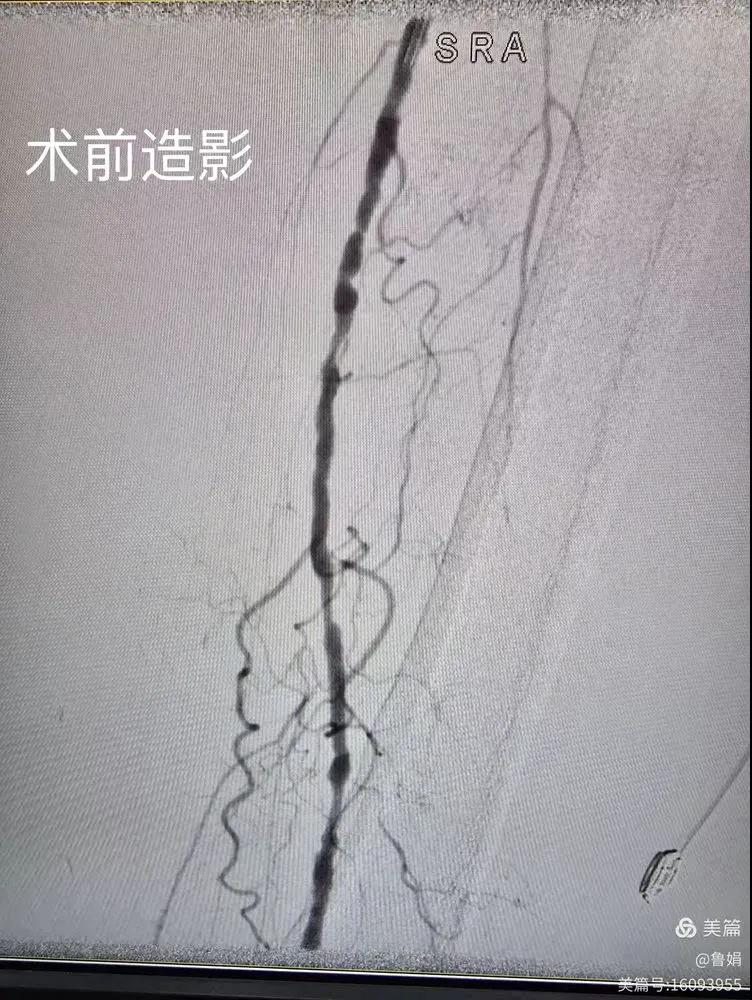

據(jù)悉,該患者,女,73歲,下肢動脈硬化閉塞癥,“以靜息痛,間歇性跛行”入院,CTA評估:股淺動脈,腘動脈間斷性多段重度狹窄,外二科血管外科團隊根據(jù)患者病情,結合檢查結果,經過科室會診后,決定對該病人行介入治療。手術由周創(chuàng)業(yè)副主任與北大一院血管外科專家郭宏杰教授聯(lián)合開展,對股淺動脈,腘動脈重度閉塞段行血管開通+藥涂球囊擴張成形,術后狹窄明顯緩解,血流恢復!